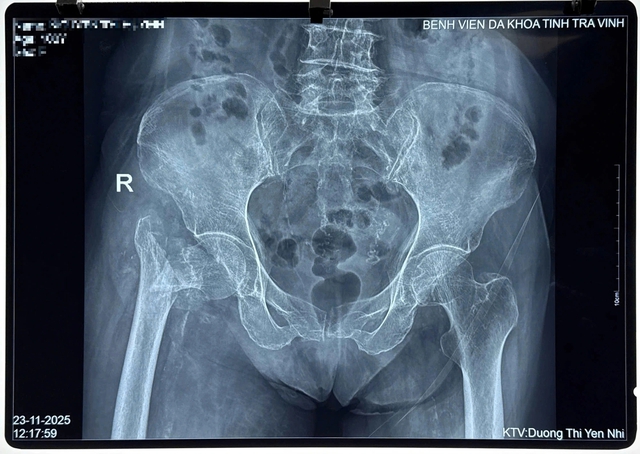

Trước đó, cụ N.T.H (100 tuổi, ngụ xã Bình Phú, Vĩnh Long) nhập viện do tai nạn sinh hoạt tại nhà. Qua thăm khám, chụp X-quang, các bác sĩ Khoa Chấn thương chỉnh hình của bệnh viện chẩn đoán bệnh nhân bị gãy nhiều mảnh đầu trên xương đùi bên phải, kèm loãng xương nặng, lão suy, viêm phổi, di chứng tai biến mạch máu não.

Hình ảnh X-quang chấn thương của cụ bà N.T.H trước khi được phẫu thuật